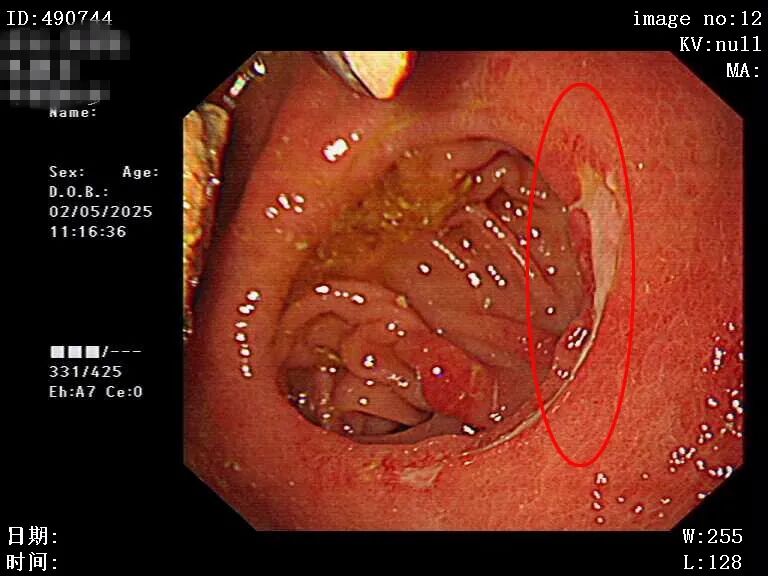

在诊疗过程中,患者不配合胃镜检查,出现反复拔镜的抗拒行为,这给诊疗工作带来了挑战。4月17日首次胃镜检查,发现齿状线上散在纵行糜烂灶,最长约15mm,相互不融合,胃底-体有大量食物残渣,考虑胃潴留,医院予禁食、胃肠减压、抑酸护胃、洗胃、补液等对症及支持治疗;26日再次进行胃镜检查,因患者不配合仅看到胃体有大量食糜潴留,食管有胃管留置,粘膜见部分食糜潴留,未见静脉曲张,继续予对症治疗;29日复查胃镜,见到胃体有潴留和一黑色球状固体,胃镜接触觉硬度高,无法绕过球状潴留物继续进入,因患者仍不配合检查而退镜,考虑胃石形成。在胃镜检查过程中发现有溃疡存在,且判断该溃疡与胃石长时间压迫密切相关。若胃石不能及时处理,溃疡面临反复出血或穿孔的极高风险,病情每拖延一刻,患者的生命健康就多一分威胁。

图片

溃疡